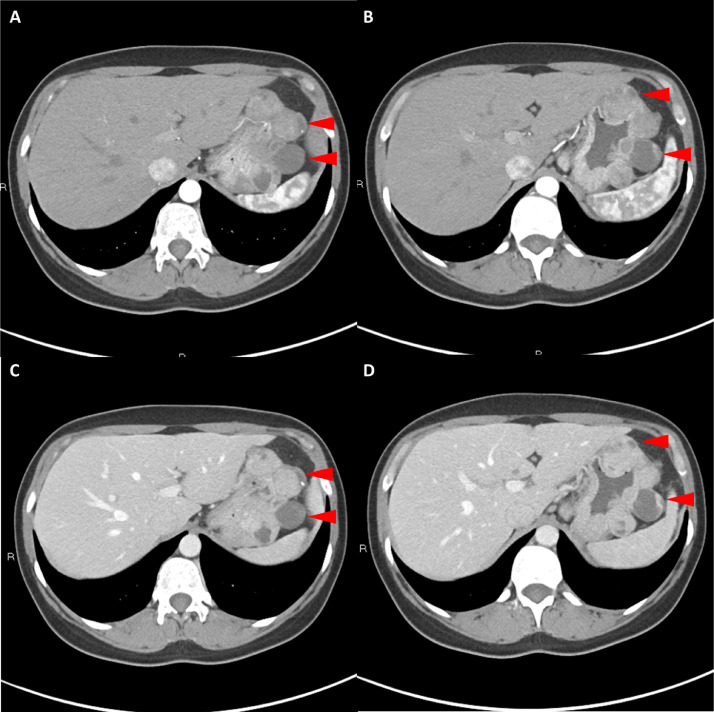

胸部、腹部和骨盆的對比增強動脈和靜脈期 CT 顯示多個圓形、主要是血管豐富的異質腫塊,具有囊性和實性成分,起源于胃底和胃體(圖 2-4)。 病變部分呈外生結構,被認為位于粘膜下層。 在頸部多發(fā)同步性副神經節(jié)瘤的情況下,賊初的鑒別診斷包括多發(fā)性副神經節(jié)瘤、多發(fā)性 GIST 以及轉移性疾病。

圖 4: 胃腸道間質瘤的三維表示。 (A 和 B)胃腸道間質瘤在動脈期和冠狀面的 3D 可視化提供了進一步的解剖細節(jié)和空間信息。